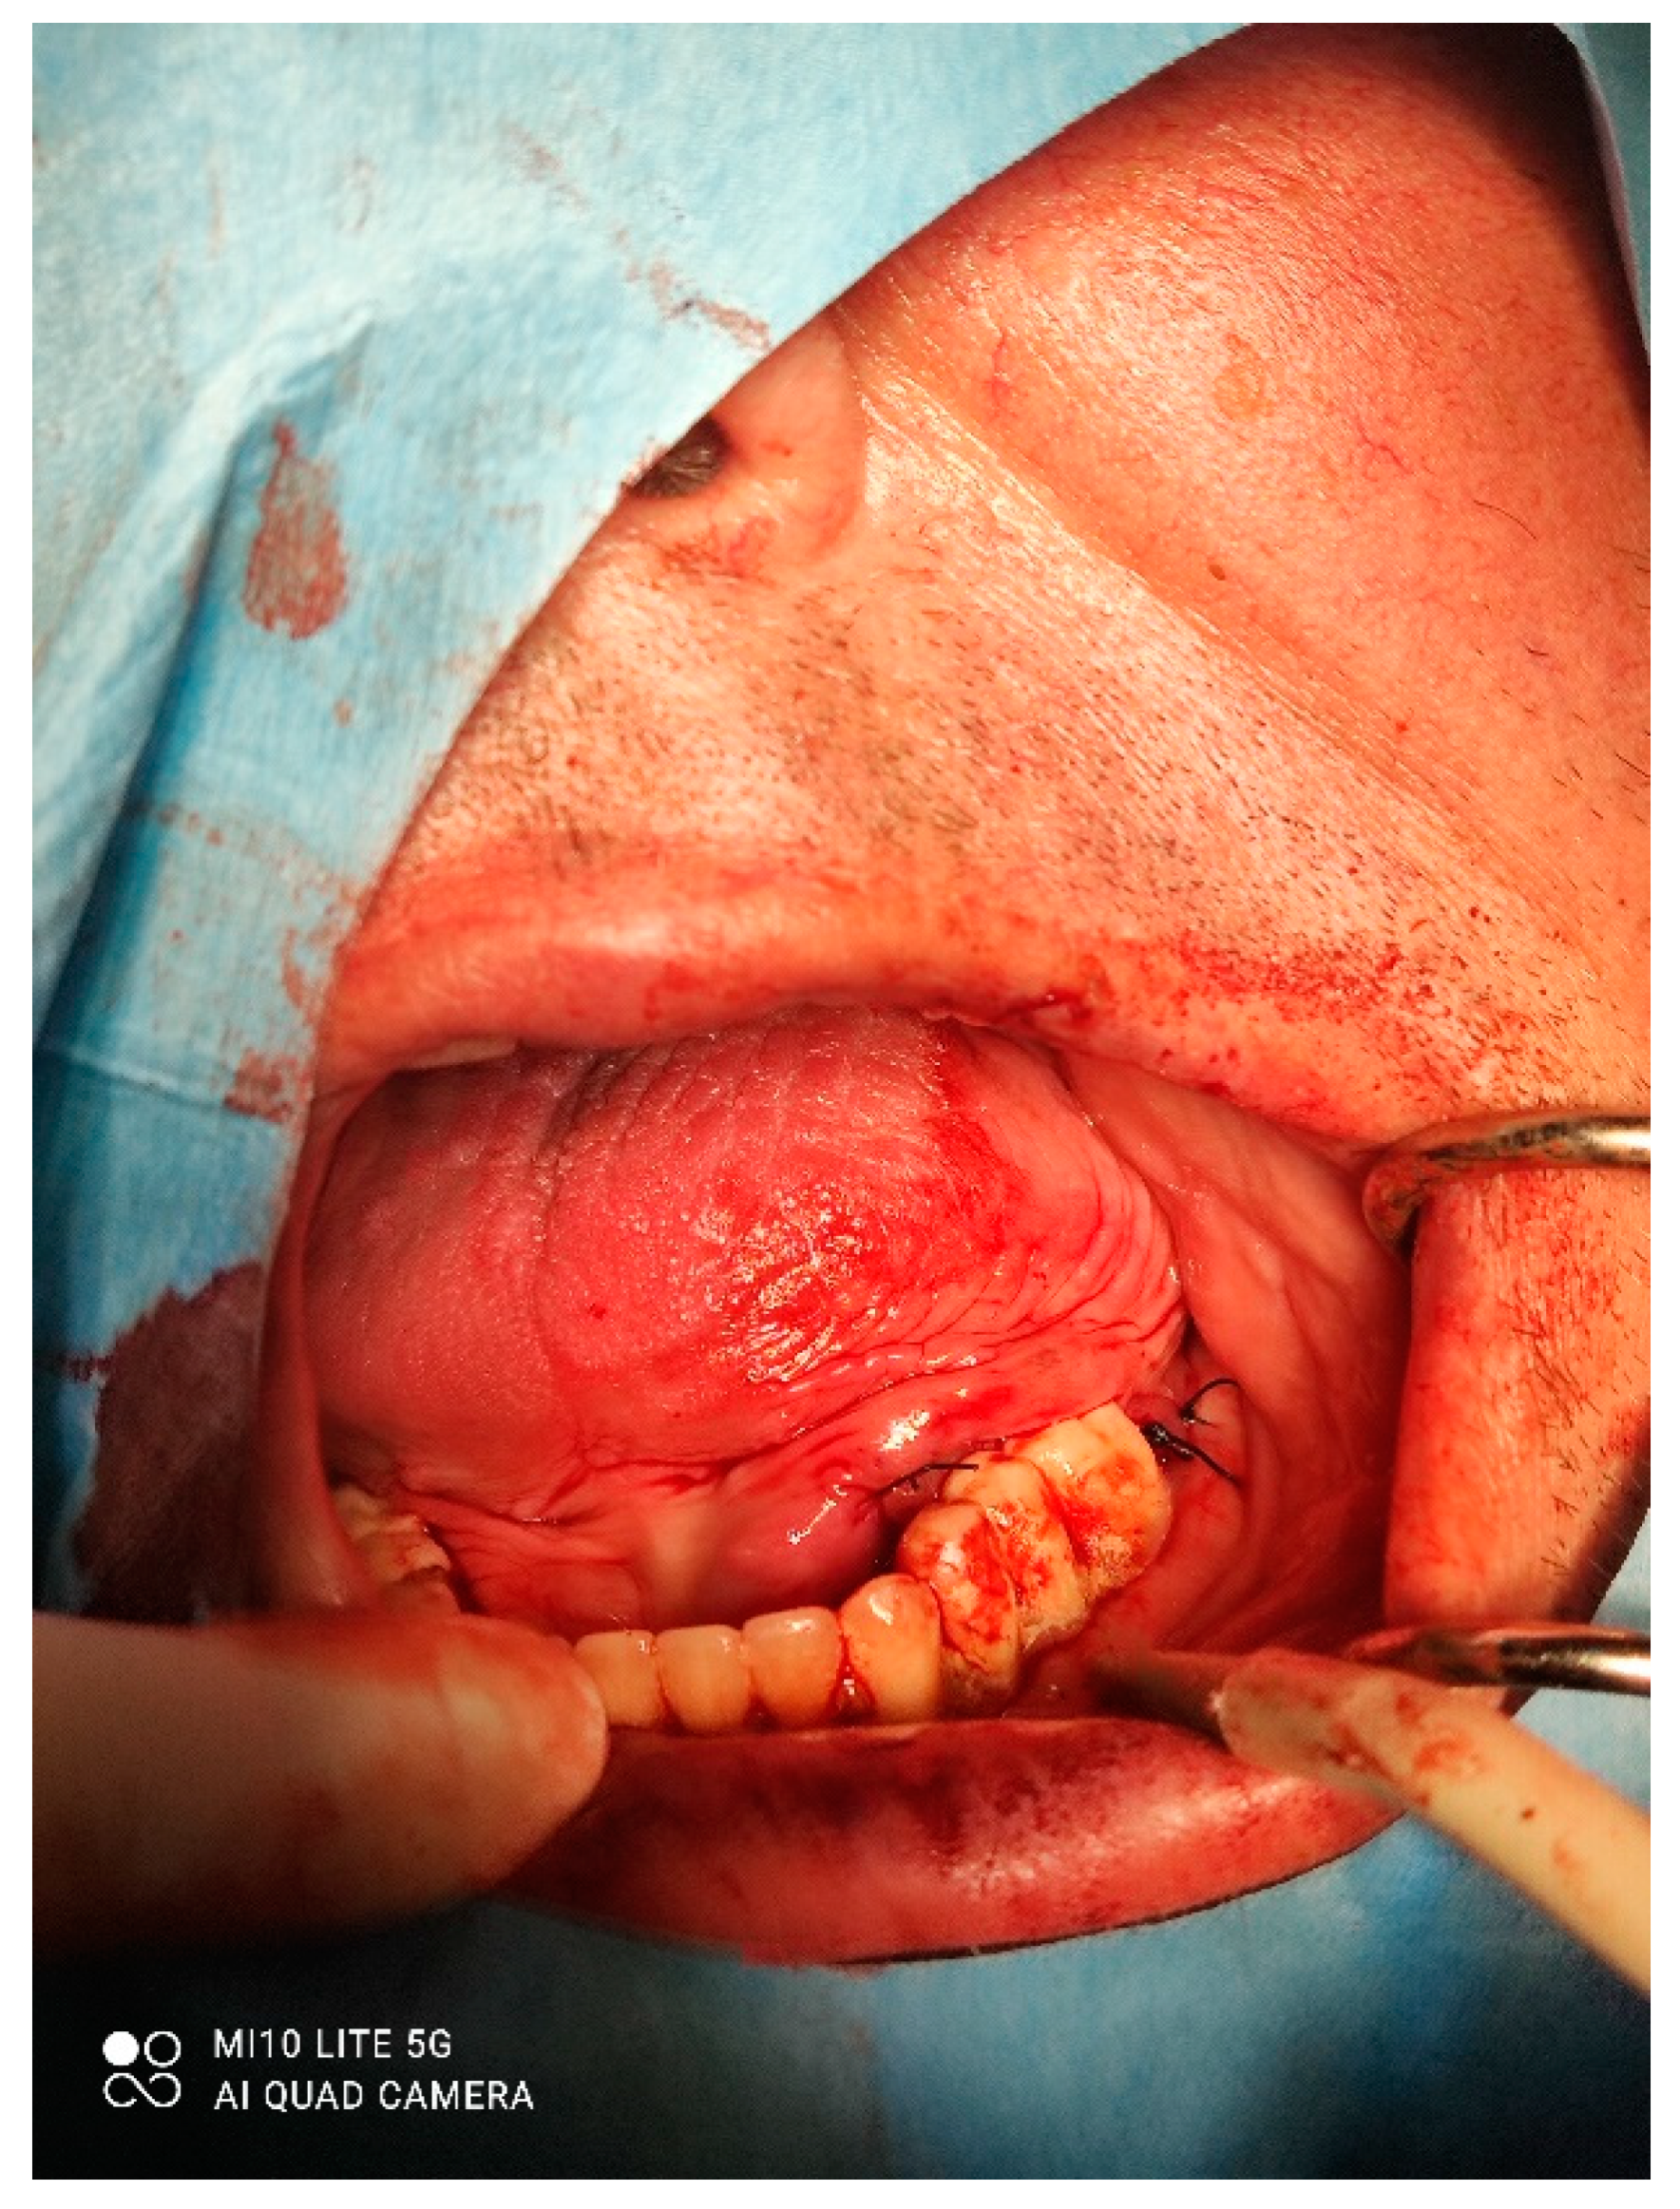

A male 70-year-old patient came to the Department of Oral Surgery, University Hospital Centre Zagreb with a voluminous fibrous mass in the distal region of the left mandible (Figure 1). The patient has two acrylic bridges on four implants. The implants were placed six months prior to admission to the clinic, before the patient noticed the appearance of the mass. The acrylic bridges are 3 months old. The patient states feeling “swelling in the back part of the left mandible three months before coming in for a checkup”. Panoramic radiograph and CBCT did not show any radiolucency, radiopaque areas or signs of periimplantitis around the implants in the bone (Figure 2). The lesion has a smooth surface, with no ulcerations. It was on a broad base connected, with the sublingual anatomical region. The patient has poor oral hygiene, smokes and consumes alcohol: about two to three glasses of wine or beer a day. The palpation of the mass indicated that it was fixed to the alveolar crest of the left mandible on a wide base and was spreading to the left sublingual area. The measured size of the mass was 3.5 × 2 cm. After conducting a clinical examination, the differential diagnosis was possible irritation fibromatosis, peripheral gigantocellular fibroma or peripheral ossifying or non-ossifying fibroma, as well as a malignant mass, and the final diagnosis will be reached after the final PHD analysis. The final decision was an excision in toto (Figure 3). The mass was approached and the layers of submucosa were divided with a scalpel and an electro knife. During operation, it was noticed that the mass has a belonging artery connected to the left sublingual area. The artery was ligated with a resorbing thread 4/0 and the mass underwent complete excision (Figure 4). Parts of the flap were left to heal per secundam, but most of the incision towards the sublingual region was stitched with a non-resorbing silk thread 4/0 (Figure 5 and Figure 6). A full hemostasis was achieved by electrocauterization of the bleeding areas. The excison was performed under local anesthesia. Clinical, medical examination and removal of sutures were performed seven days after surgery (Figure 7).

Figure 3. Removal of the mass.